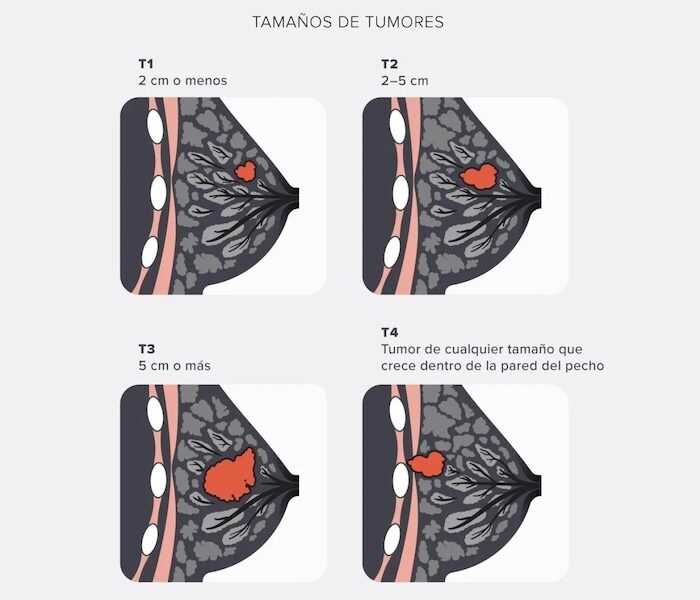

- Patologías ginecológicas frecuentes como quistes ováricos, endometriosis y miomas.

- Cirugías ginecológicas ambulatorias (ej. extirpación de quistes, miomas, lesiones benignas).